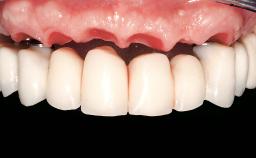

Immediate Loading of Eight Implants in the Maxilla and Six Implants in the Mandible and Final Restoration with Three-Unit and Four-Unit FDPs

Extensive scientific evidence has confirmed that immediately loaded implants with fixed full-arch provisional restorations can osseointegrate with success rates similar to conventionally or delayed loaded implants. A number of immediate-provisionalization techniques for edentulous jaws have been described. Some protocols differ when it comes to prefabricated provisional templates versus complete denture conversion; intrasurgical impressions versus direct relining; and cemented versus screw-retained provisional restorations. In this context, complete-denture conversion has been proposed for either intrasurgical impressions or direct relining. Another possibility is the utilization of a prefabricated provisional to be adapted either in the mouth (by direct relining) or in the laboratory (on a working model obtained from an intrasurgical impression).

Prosthesis Type FDP

SAC Level Complex

Defining Characteristics Fully edentulous upper jaw to be rehabilitated with an implant-borne fixed dental prosthesis

Loading Protocol Immediate